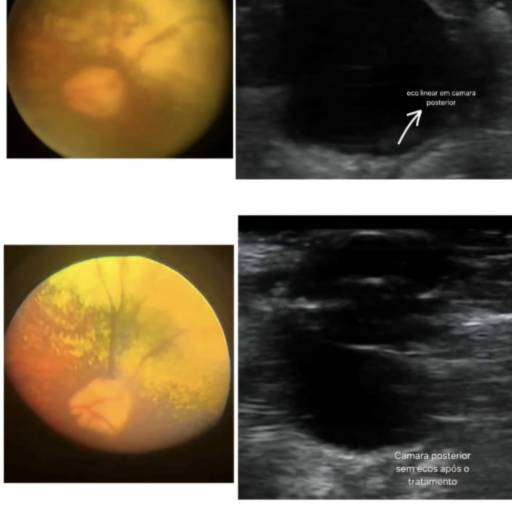

Clínicas VeterináriasO ultrassom ocular é um exame avançado utilizado para investigar alterações no globo ocular e diagnosticar problemas de visão com precisão. Na Clinicão Veterinária, em Três Lagoas – MS, esse recurso é aplicado para avaliar a câmara posterior dos olhos, detectar descolamentos de retina e identificar nódulos retrobulbares, garantindo maior segurança nos diagnósticos.

Esse exame é indicado para animais que apresentam sinais de perda de visão, alterações oculares súbitas, suspeita de tumores ou complicações em estruturas internas do olho. Com mais de 27 anos de experiência em oftalmologia veterinária, a Dra. Claudia Boraschi alia tecnologia de ponta e conhecimento especializado para oferecer diagnósticos confiáveis e atendimento diferenciado.